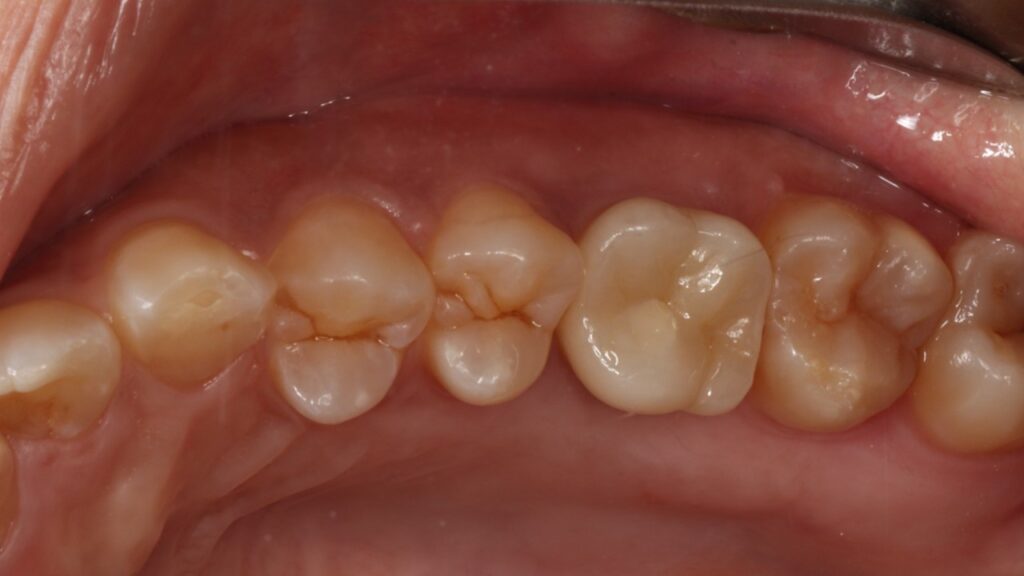

治療後

4ヵ月で最終的なセラミック冠を装着しています。

CTスキャンで確認してみても上顎洞炎もきれいに治っていることが分かります。

歯が割れた原因は無意識の噛みしめや歯ぎしりなので、就寝時にマウスピースを使うなどの対応もしています。